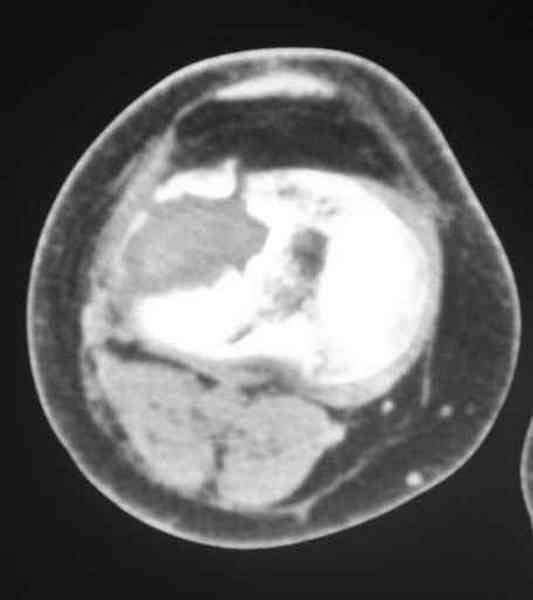

Уважаемый Абдурашид. Если нет противопоказаний , то из оперативных способов, я бы рекомендовал следующие: Полное замещение наружного мыщелка аллотрансплантатом либо открытая репозиция с элевацией и замещение дефекта ауто или аллокостью. В Ваших условиях , я бы рекомендовал второй способ. Во-время элевации необходимо разъединить фрагменты со стороны сустава ( надсечь скальпелем по линиям перелома, а затем тонким остеотомом их разъединить. При помощи долота произвести неполную остеотомию ( захватите не менее 1,5 - 2 см губчатой кости и поднять фрагменты, визуально отрепонировать и фиксировать 2-3 спицами. Дефект заместить костным ауто или аллатрансплантатом. Окончательная стабилизация пластиной ( лучше с угловой стабильностью, либо АВФ - позволит спокойно устранить угловую деформацию.

Недавно поступила больная через 1,5- 2 месяца.